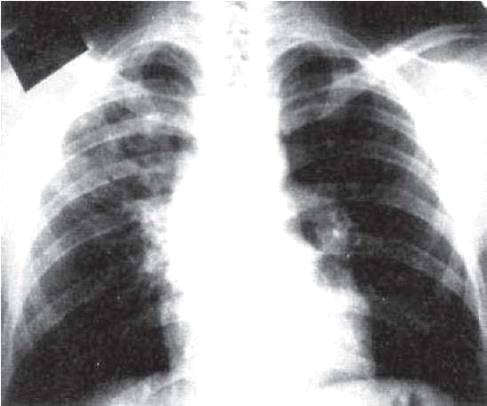

Симптомы и лечение инфильтративного туберкулеза легких

Раздел: Снимки-откровения